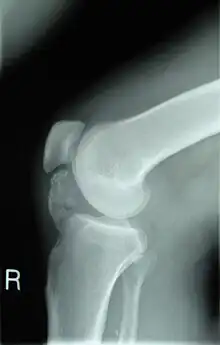

| Lateral radiograph of the knee demonstrating ossification in the peritendinous tissues in a patient with osteochondroma. | |